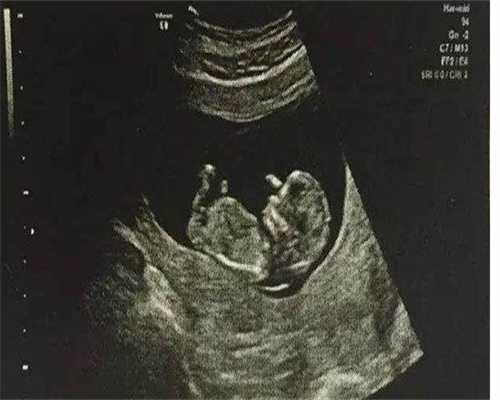

427个回答几个月b超看男女准确率高?b超单子、图片看男女教程别错过